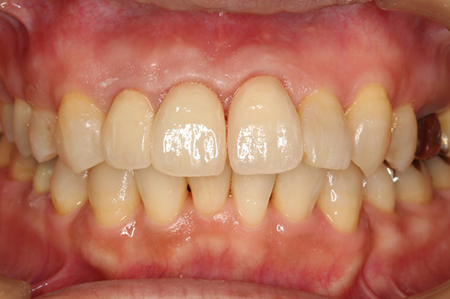

前から見ても歯が欠けてしまい、歯茎も赤く腫れてしまっているのが分かります。

処置後、非常に審美的な補綴物が入ったことが分かるかと思います。

非常に審美的な治療が出来ました。